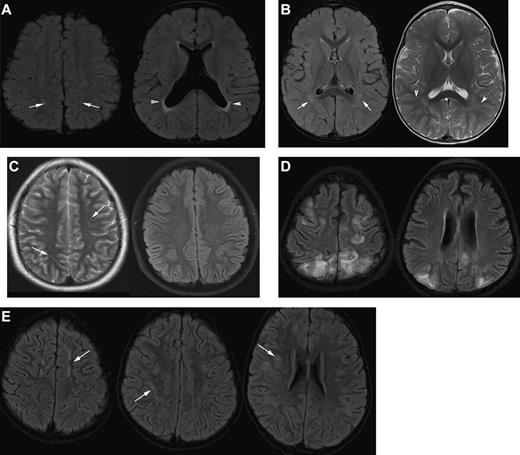

MRI in sickle cell disease. (A) Coronal T1-weighted MRI, (B) coronal T2-weighted MRI, and (C-H) axial T2-weighted MRI in patients with homozygous SCA. (A-C) Silent cerebral infarction (white arrows) in the parietal white matter in a 10-year-old girl with headache. (D) Three years later, there is progressive atrophy on MRI in the context of intermittent ataxia and squint. (E-H) Four cases associated with acute illness. (E) Silent cerebral infarction (black arrows) in the watershed regions between the anterior, middle, and posterior regions, including the deep white matter, in a patient who had previously had posterior reversible encephalopathy syndrome in the context of cyclosporine treatment for nephrotic syndrome. (F) Bilateral watershed infarction in a child who had seizures in the context of a facial infection. Motor examination was normal but his IQ was reduced by 30 points compared with premorbid testing. (G) Encephalomalacia after sagittal sinus thrombosis secondary to pneumococcal meningitis. (H) Occipital infarction after acute chest crisis. A homonymous visual field defect was detected after the infarct was noted on MRI.